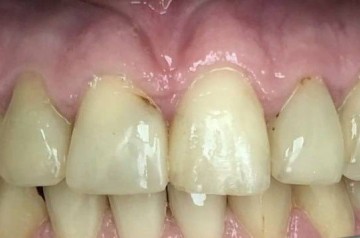

Пациент, 54 года. Замена старых металлических протезов на диоксид циркония.